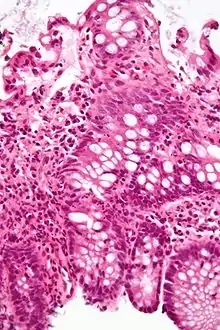

Micrograph showing intestinal crypt branching, a histopathological finding of chronic colitides. H&E stain.

Micrograph showing intestinal crypt branching, a histopathological finding of chronic colitides. H&E stain. Micrograph showing crypt inflammation. H&E stain.

Micrograph showing crypt inflammation. H&E stain. Crypt abscess. H&E stain.

Crypt abscess. H&E stain.